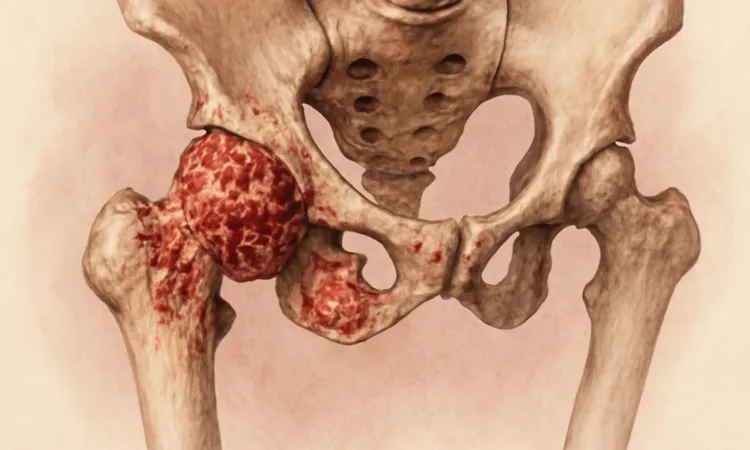

Новообразования тазобедренного сустава можно разделить на две большие категории: доброкачественные и злокачественные. Каждая из этих категорий включает в себя различные подвиды опухолей, которые имеют свои особенности и требуют особого подхода. Перечисление основных видов новообразований представлено ниже.

Доброкачественные опухоли:

- Остеохондрома – относительно распространенный вид, характеризующийся избыточным разрастанием хряща и костной ткани.

- Синовиальная саркома – образование, возникшее из суставной оболочки, может приводить к болевым ощущениям и ограничению подвижности.

- Аденома – опухоль, развивающаяся в мягких тканях, чаще всего без симптомов на ранних стадиях.

Злокачественные опухоли:

- Остеосаркома – агрессивное образование, часто встречается у молодых людей, вызывает сильную боль и отек.

- Саркома Юинга – опухоль, которая обычно поражает кости и мягкие ткани, требует незамедлительного лечения.

- Метастатические опухоли – раковые образования, которые распространились в тазобедренный сустав из других органов, таких как легкие или молочная железа.

Каждый из этих видов имеет свои уникальные проявления и требует индивидуального подхода к диагностике и лечению. Определение типа новообразования является ключевым фактором в выборе оптимального метода терапии.